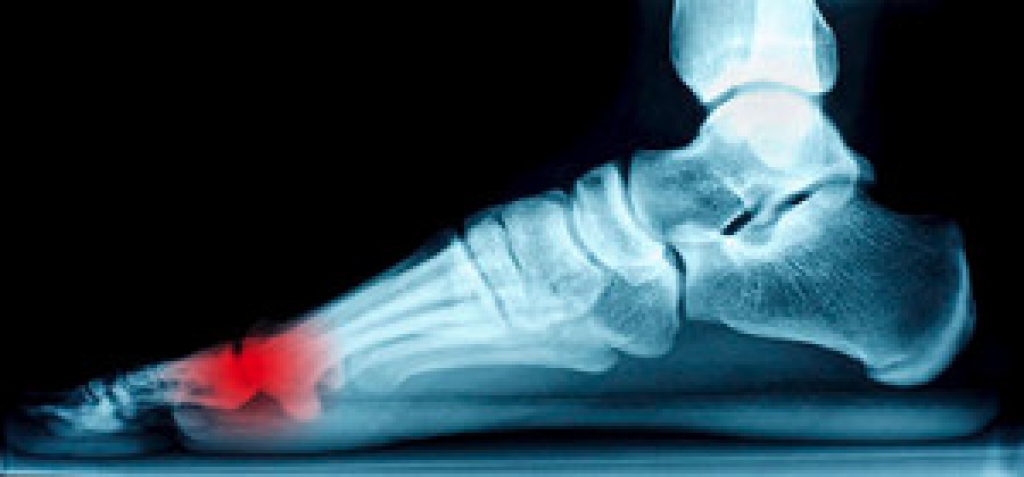

Am I at Risk for Plantar Fasciitis?

Plantar fasciitis is a very common foot problem, especially among runners. It occurs when the plantar fascia, the ligament that runs along the bottom of the foot and connects the heel bone to the toes, becomes inflamed due to repeated injury or overuse. You may be at an increased risk for developing plantar fasciitis if you are a highly active runner, stand for prolonged periods of times, have tight calves or a decreased range of motion in your ankles, have flat or high arched feet, or are obese. Fortunately, there are many treatments for plantar fasciitis, including resting the foot, performing foot stretches, and modifying your activities or footwear. If you believe that you are at risk for developing plantar fasciitis, please consult with a podiatrist.

Plantar fasciitis can be very painful and inconvenient. If you are experiencing heel pain or symptoms of plantar fasciitis, contact Dr. Robbi Young  from Grand Haven Foot & Ankle. Our doctor can provide the care you need to keep you pain-free and on your feet.

What Is Plantar Fasciitis?

Plantar fasciitis is the inflammation of the thick band of tissue that runs along the bottom of your foot, known as the plantar fascia, and causes mild to severe heel pain.

What Causes Plantar Fasciitis?

• Excessive running

• Non-supportive shoes

• Overpronation

• Repeated stretching and tearing of the plantar fascia

How Can It Be Treated?

• Conservative measures – anti-inflammatories, ice packs, stretching exercises, physical therapy, orthotic devices

• Shockwave therapy – sound waves are sent to the affected area to facilitate healing and are usually used for chronic cases of plantar fasciitis

• Surgery – usually only used as a last resort when all else fails. The plantar fascia can be surgically detached from the heel

While very treatable, plantar fasciitis is definitely not something that should be ignored. Especially in severe cases, speaking to your doctor right away is highly recommended to avoid complications and severe heel pain. Your podiatrist can work with you to provide the appropriate treatment options tailored to your condition.

Causes of Heel Pain

Heel pain can be debilitating and can form due to a variety of reasons. The most common cause of heel pain occurs when the band of tissue that connects the heel bone to the toes, known as the plantar fascia, becomes inflamed causing plantar fasciitis. When the Achilles tendon becomes inflamed Achilles tendonitis may occur, and this can lead to heel pain too. Heel pain can also be caused by a natural wearing of the fat pad which is connected to the heel, as well as stress fractures, bursitis, or a variety of diseases such as arthritis and gout. If you are suffering from heel pain it is highly recommended that you visit a podiatrist who can determine what the cause of your pain is. A podiatrist will be able to provide a proper treatment plan for your heel pain as well.

Many people suffer from bouts of heel pain. For more information, contact Dr. Robbi Young of Grand Haven Foot & Ankle. Our doctor can provide the care you need to keep you pain-free and on your feet.

Heel pain is often associated with plantar fasciitis. The plantar fascia is a band of tissues that extends along the bottom of the foot. A rip or tear in this ligament can cause inflammation of the tissue.

Achilles tendonitis is another cause of heel pain. Inflammation of the Achilles tendon will cause pain from fractures and muscle tearing. Lack of flexibility is also another symptom.

Heel spurs are another cause of pain. When the tissues of the plantar fascia undergo a great deal of stress, it can lead to ligament separation from the heel bone, causing heel spurs.

Why Might Heel Pain Occur?

• Wearing ill-fitting shoes

• Wearing non-supportive shoes

• Weight change

Treatments

Heel pain should be treated as soon as possible for immediate results. Keeping your feet in a stress-free environment will help. If you suffer from Achilles tendonitis or plantar fasciitis, applying ice will reduce the swelling. Stretching before an exercise like running will help the muscles. Using all these tips will help make heel pain a condition of the past.